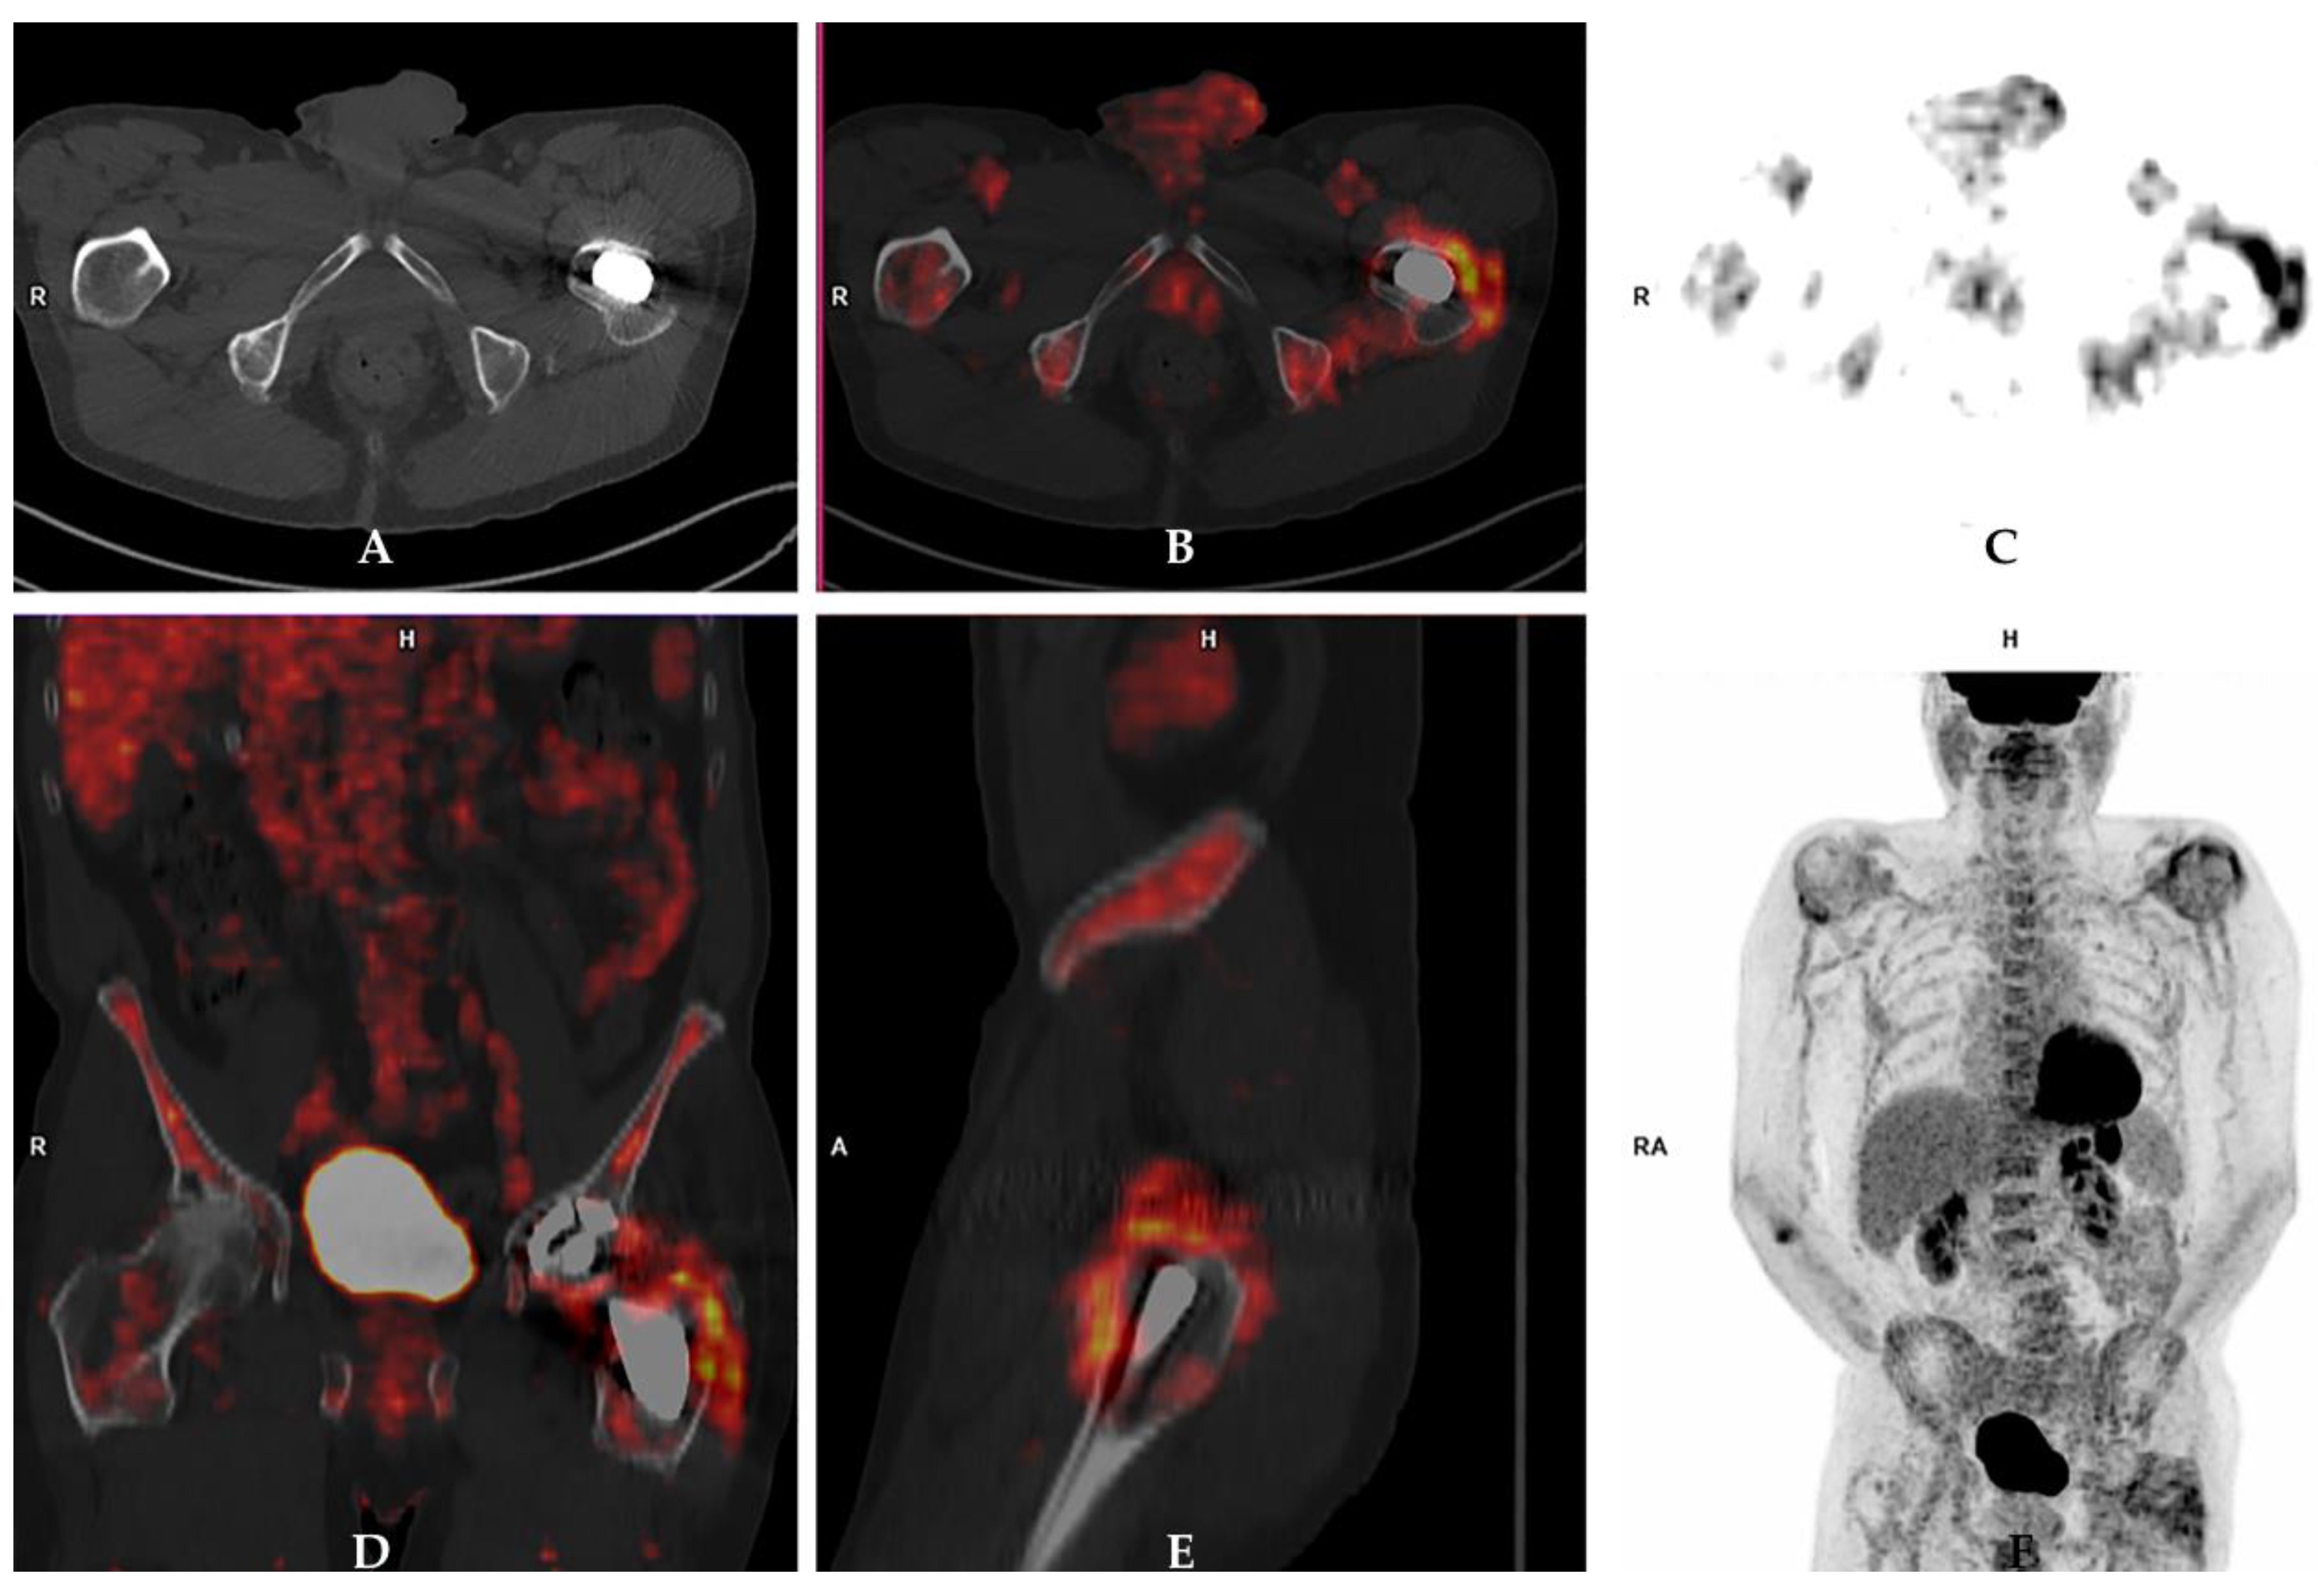

4.5. FDG PET/CT

5.8. What Is the Role of [18F]-FDG-PET/CT to Diagnose a PJI (Is a Negative Scan Sufficient to Exclude a PJI)?